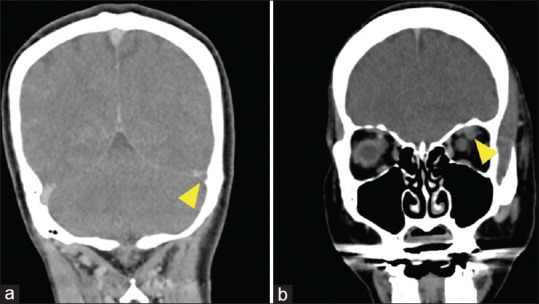

勒米尔综合征是一种罕见的疾病,以颈内静脉血栓性静脉炎和远处器官转移为特征。该病发生在喉部或牙齿部位的厌氧菌感染之后;中枢神经系统受累的情况并不多见。一名 50 岁的妇女出现意识障碍。发病前,她因牙痛接受了数天的牙科治疗。对比增强计算机断层扫描(CT)显示头颈部有脓肿,颈内静脉有大量血栓,诊断为莱米埃尔综合征。经过手术引流和抗菌治疗后,症状有所好转,患者于第 58 天出院。在这个病例中,由于大量脑静脉血栓导致静脉充血,并发了静脉中风,从而并发了莱米埃尔综合征。莱米埃尔综合征患者可能因血栓导致静脉中风,磁共振成像或 CT 静脉相成像可帮助诊断。

Lemierre's syndrome is a rare disease characterized by thrombophlebitis of the internal jugular vein and metastasis to distant organs. It occurs after an anaerobic infection of the larynx or dental region; the central nervous system involvement is infrequent. A 50-year-old woman presented with impaired consciousness. She had undergone several days of dental treatment for a toothache before presentation. Contrast-enhanced computed tomography (CT) revealed a head-and-neck abscess and a massive thrombus in the internal jugular vein, and a diagnosis of Lemierre's syndrome was made. After symptoms improved with surgical drainage and antimicrobial therapy, the patient was discharged on day 58. In this case, Lemierre's syndrome was complicated by a venous stroke caused by venous congestion due to a massive cerebral venous thrombus. Venous stroke due to thrombi may occur in patients with Lemierre's syndrome, and magnetic resonance imaging or CT with venous phase imaging may aid in the diagnosis.